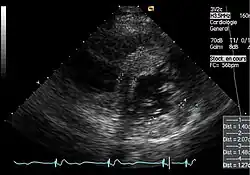

Die linksventrikulären strukturellen Veränderungen des Herzens finden sich bei Morbus-Fabry-Patienten häufig. Mittels Echokardiografie (Ultraschalluntersuchung des Herzens) oder kardialer Magnetresonanztomographie (MRT) können die meist konzentrischen Hypertrophien[80][81] sichtbar gemacht werden. Da mit zunehmendem Alter durch die Ersatzfibrose die linksventrikuläre Hinterwand des Herzens immer dünner wird, ist die Messung der Septumdicke – das ist die Stärke der Scheidewand zwischen linker und rechter Herzhälfte – besonders wichtig. Unabhängig von den strukturellen Veränderungen scheint die Systole, die Phase, in der das Blut aus der linken und rechten Herzkammer herausgepresst wird, bei der Messung mit konventionellen Methoden weitgehend erhalten zu bleiben.[80][81][82][91] Die durch Morbus Fabry verursachte Kardiomyopathie ist durch eine reduzierte Kontraktion und Relaxation des Herzmuskels gekennzeichnet. Gewebedoppler (sowohl tissue velocity imaging als auch strain rate imaging) kann die Herzmuskelfunktion quantifizieren.[7][92] Mit dieser Methode kann die Kardiomyopathie noch vor der Entwicklung einer linksventrikulären Hypertrophie diagnostiziert werden.[91][93]

- Echokardiografien von Patienten mit Morbus Fabry

-

Parasternale lange Achse: Deutlich sichtbar die linksventrikuläre Hypertrophie mit erhöhter Septumdicke. -

Parasternale kurze Achse: Die Aufnahme zeigt ebenfalls eine linksventrikuläre Hypertrophie. -

Gewebedoppler-Echokardiographie des Mitralanulus (Mitralring) mit nahezu normaler systolischer Funktion